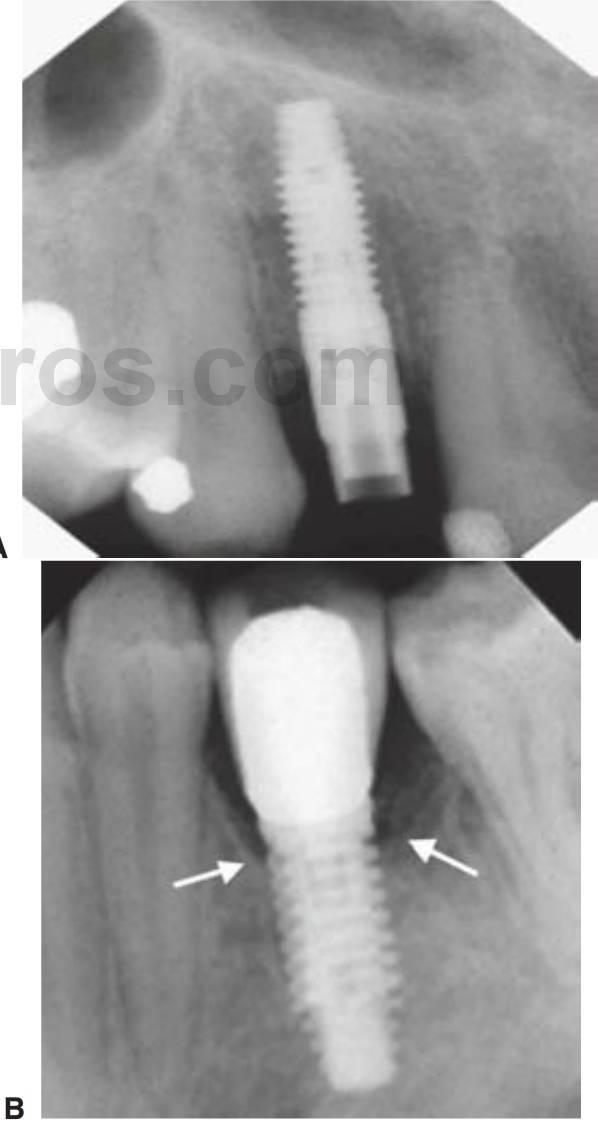

Imágenes posquirúrgicas inmediatas

Para emplear una imagen de base para evaluarla frente a futuras películas, se debería de tomar una radiografía convencional (periapical o panorámica) de manera posquirúrgica (fig. 3-24). Se pueden emplear herramientas de imagen adicionales para evaluar una zona de seguridad alrededor de las estructuras vitales.

Evaluación de los cambios de hueso alveolar

En términos radiográficos, la pérdida o falta de integración se suele indicar como una línea radiolúcida alrededor del implante. En cualquier caso, se pueden hacer falsos diagnósticos cuando el tejido blando alrededor del implante no es suficientemente amplio para superar la resolución de la modalidad radiográfica empleada. Se pueden hacer también diagnósticos positivos falsos cuando se produce el «efecto de banda de Mach» como resultado de un área de menor densidad radiográfica adyacente a un área de alta densidad (implante), lo que resulta en un área más radiolúcida que la realmente presente. En cualquier caso, los estudios han demostrado que la posibilidad de producir un efecto de banda Mach es significativamente menor con los procesados digitales de imagen. Adicionalmente, la radiografía digital ha demostrado tener la ventaja respecto de otras radiografías convencionales en relación con la «mejora del borde», que es la habilidad de detectar un espacio entre el implante y el hueso alrededor suyo (fig. 3-27).